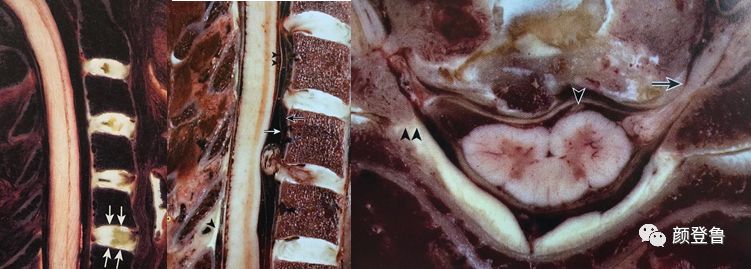

窦椎神经也叫脊膜支或返神经,是由脊神经发出的一支分支,起于背神经节之上,通过椎间孔之后又重返椎管,它在脊神经分出前支和后支之前分出,与主干反向走行,有交感神经的分支加入,经椎间孔进入椎管。

在颈部的窦椎神经主干直接与椎间盘纤维环的后面相邻,在颈部的椎间盘向后外方向突出时,可直接刺激窦椎神经的主干。窦椎神经有交感神经的分支加入,经椎间孔进入椎管。

在椎管内,窦椎神经分成较大的升支和较小的降支,各相邻的升支与降支相互吻合,形成脊膜前丛和脊膜后丛,遍布于脊膜全长,并伸入颅内。

窦椎神经分布于脊膜、椎管、椎管内所有组织、椎间关节囊、椎骨的韧带及脊髓的血管都有窦椎神经分布,在后纵韧带、硬脊膜前部和神经根袖内分布最密集。